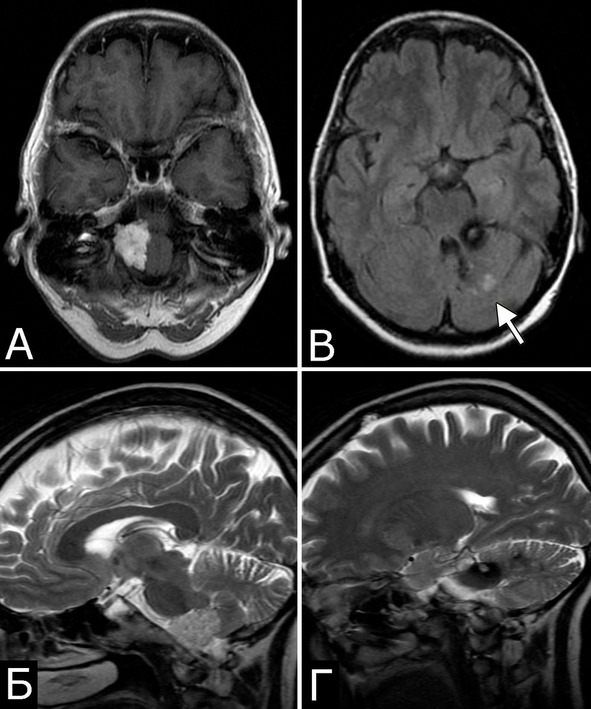

Рис. 4. II. Б-ная С-ва, 51 г. Сочетаннная патология мозга:

1. Опухоль (менингиома) мосто-мозжечкового угла справа (А – МРТ с введением КВ, режим Т1, аксиальная проекция, Б – МРТ, режим Т2, сагиттальная проекция); 2. КМ верхнее-медиальных отделов левой гемисферы мозжечка (В, Д – МРТ, режим Т1, аксиальная проекция, Г, Е – МРТ, режим Т2, сагиттальная проекция. Стрелкой указана дополнительная тень гиперинтенсивного сигнала – косвенный признак венозной ангиомы). 3. Венозная ангиома (стрелки) левой гемисферы мозжечка (Ж, З – прямая АГ, венозная фаза). Клиническое течение: в течение нескольких лет – сильные стреляющие и ноющие боли в левой половине лица и головы

Представляет интерес наблюдение, в котором выявлены сразу три типа патологии – кавернозная мальформация, венозная ангиома и опухоль, причем все образования располагались в задней черепной ямке (рис. 4).